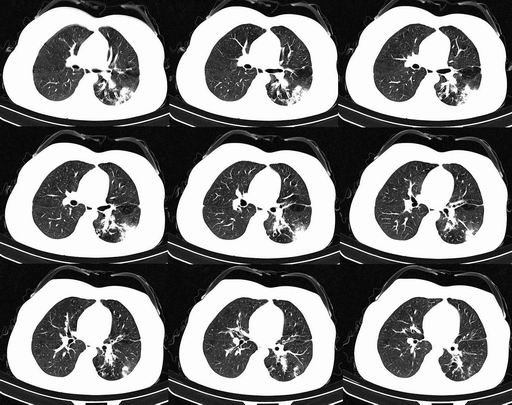

鉴别诊断:

①周围型肺癌:边缘可有较深分叶,细短毛刺、血管集束征,邻近胸膜凹陷征,胸水、肺门、纵隔淋巴结肿大,痰细胞学检查发现癌细胞。

②结核球:密度较高可见斑点钙化或边缘性腔洞,周围有卫星灶,胸膜钙化,增强扫描不强化或边缘强化。

③球型肺炎:中央密度高边缘较淡,呈晕样改变;广泛胸膜增厚;病灶呈方形,周围可见斑状、薄片影,周围血管纹理多、增粗,无僵直和牵拉;临床上有起病急变化快,抗炎治疗效果明显,病程短等特征。